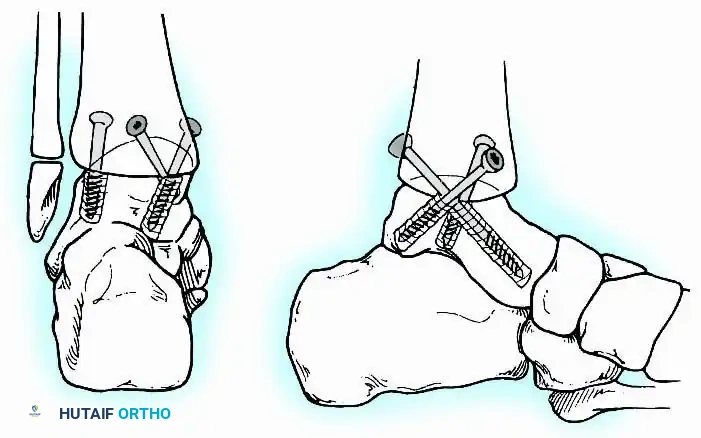

Internal fixation is currently the preferred method for uncomplicated ankle arthrodesis due to higher union rates, superior patient comfort, and the elimination of pin-tract infections. Biomechanical studies demonstrate that crossed, large-diameter (6.5 mm or 7.3 mm) cannulated cancellous screws provide exceptional resistance to shear and torsional forces.

A standard construct involves two or three screws:

1. A "home run" screw directed from the posterior malleolus into the anterior neck of the talus.

2. A screw from the medial malleolus into the lateral body of the talus.

3. A screw from the anterolateral tibia into the medial talar body.

In cases of severe osteopenia or when extending the fusion to the subtalar joint (Tibiotalocalcaneal Arthrodesis), retrograde intramedullary nailing provides a load-sharing construct with superior bending stiffness.